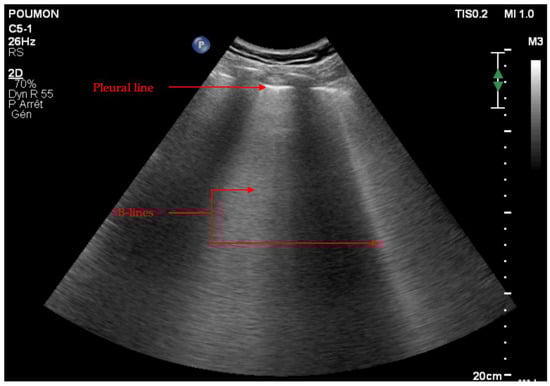

Artifacts

Real Images